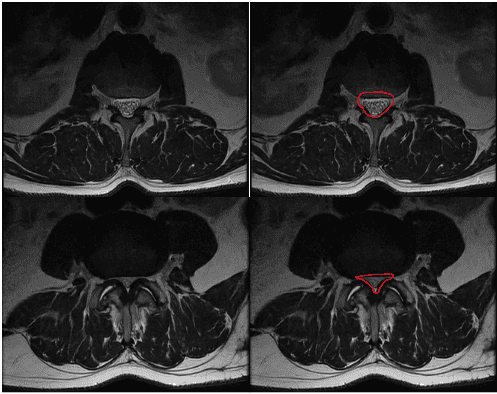

MRI of the lumbar spine. The top images show a normal diameter spinal canal without any narrowing, outlined in red on the right.

The bottom images show a spinal canal with narrowing around the nerve roots, outlined in red on the right. This is called lumbar stenosis.